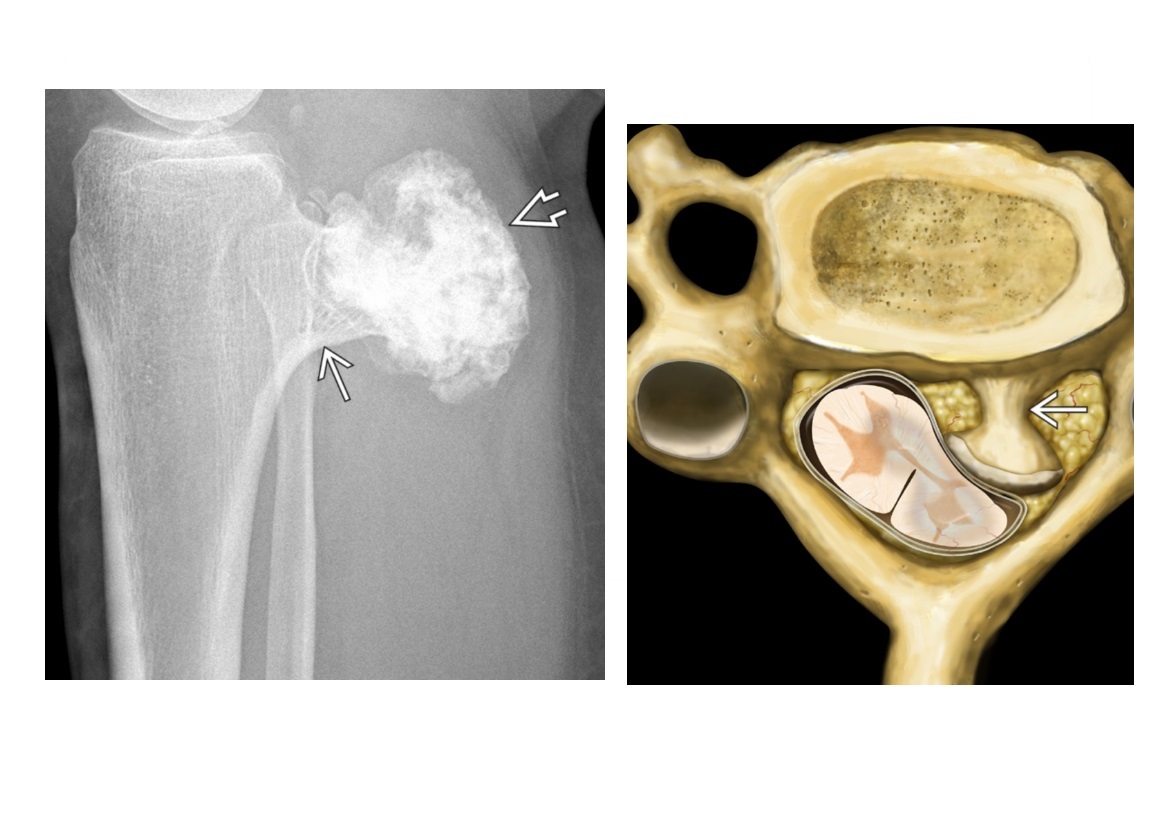

Osteochondroma

points away from the joint

Pedunculated lesion arising from surface of bone with continuity of normal cortex and marrow

Metaphysis/metaphyseal equivalents (rarely diaphysis)

Multiple =

Diaphyseal aclasia/Multiple Hereditary Exostoses - Metaphysis region of tubular bones of extremities

Cap > 1.5cm ??? chondrosarcomatous transformation

ng. avian spur points towards the joint